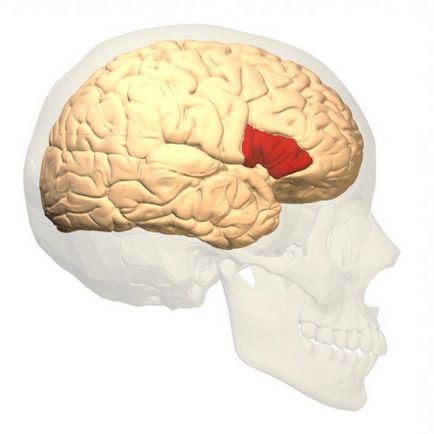

zona Broca

V-ați gândit vreodată despre cazul în care regiunea responsabilă pentru capacitatea de a vorbi? zona Broca este situată în partea din spate scăzut al treilea girusul frontal al emisferei stângi la persoanele care scriu cu mâna dreaptă. Stângacilor opus.